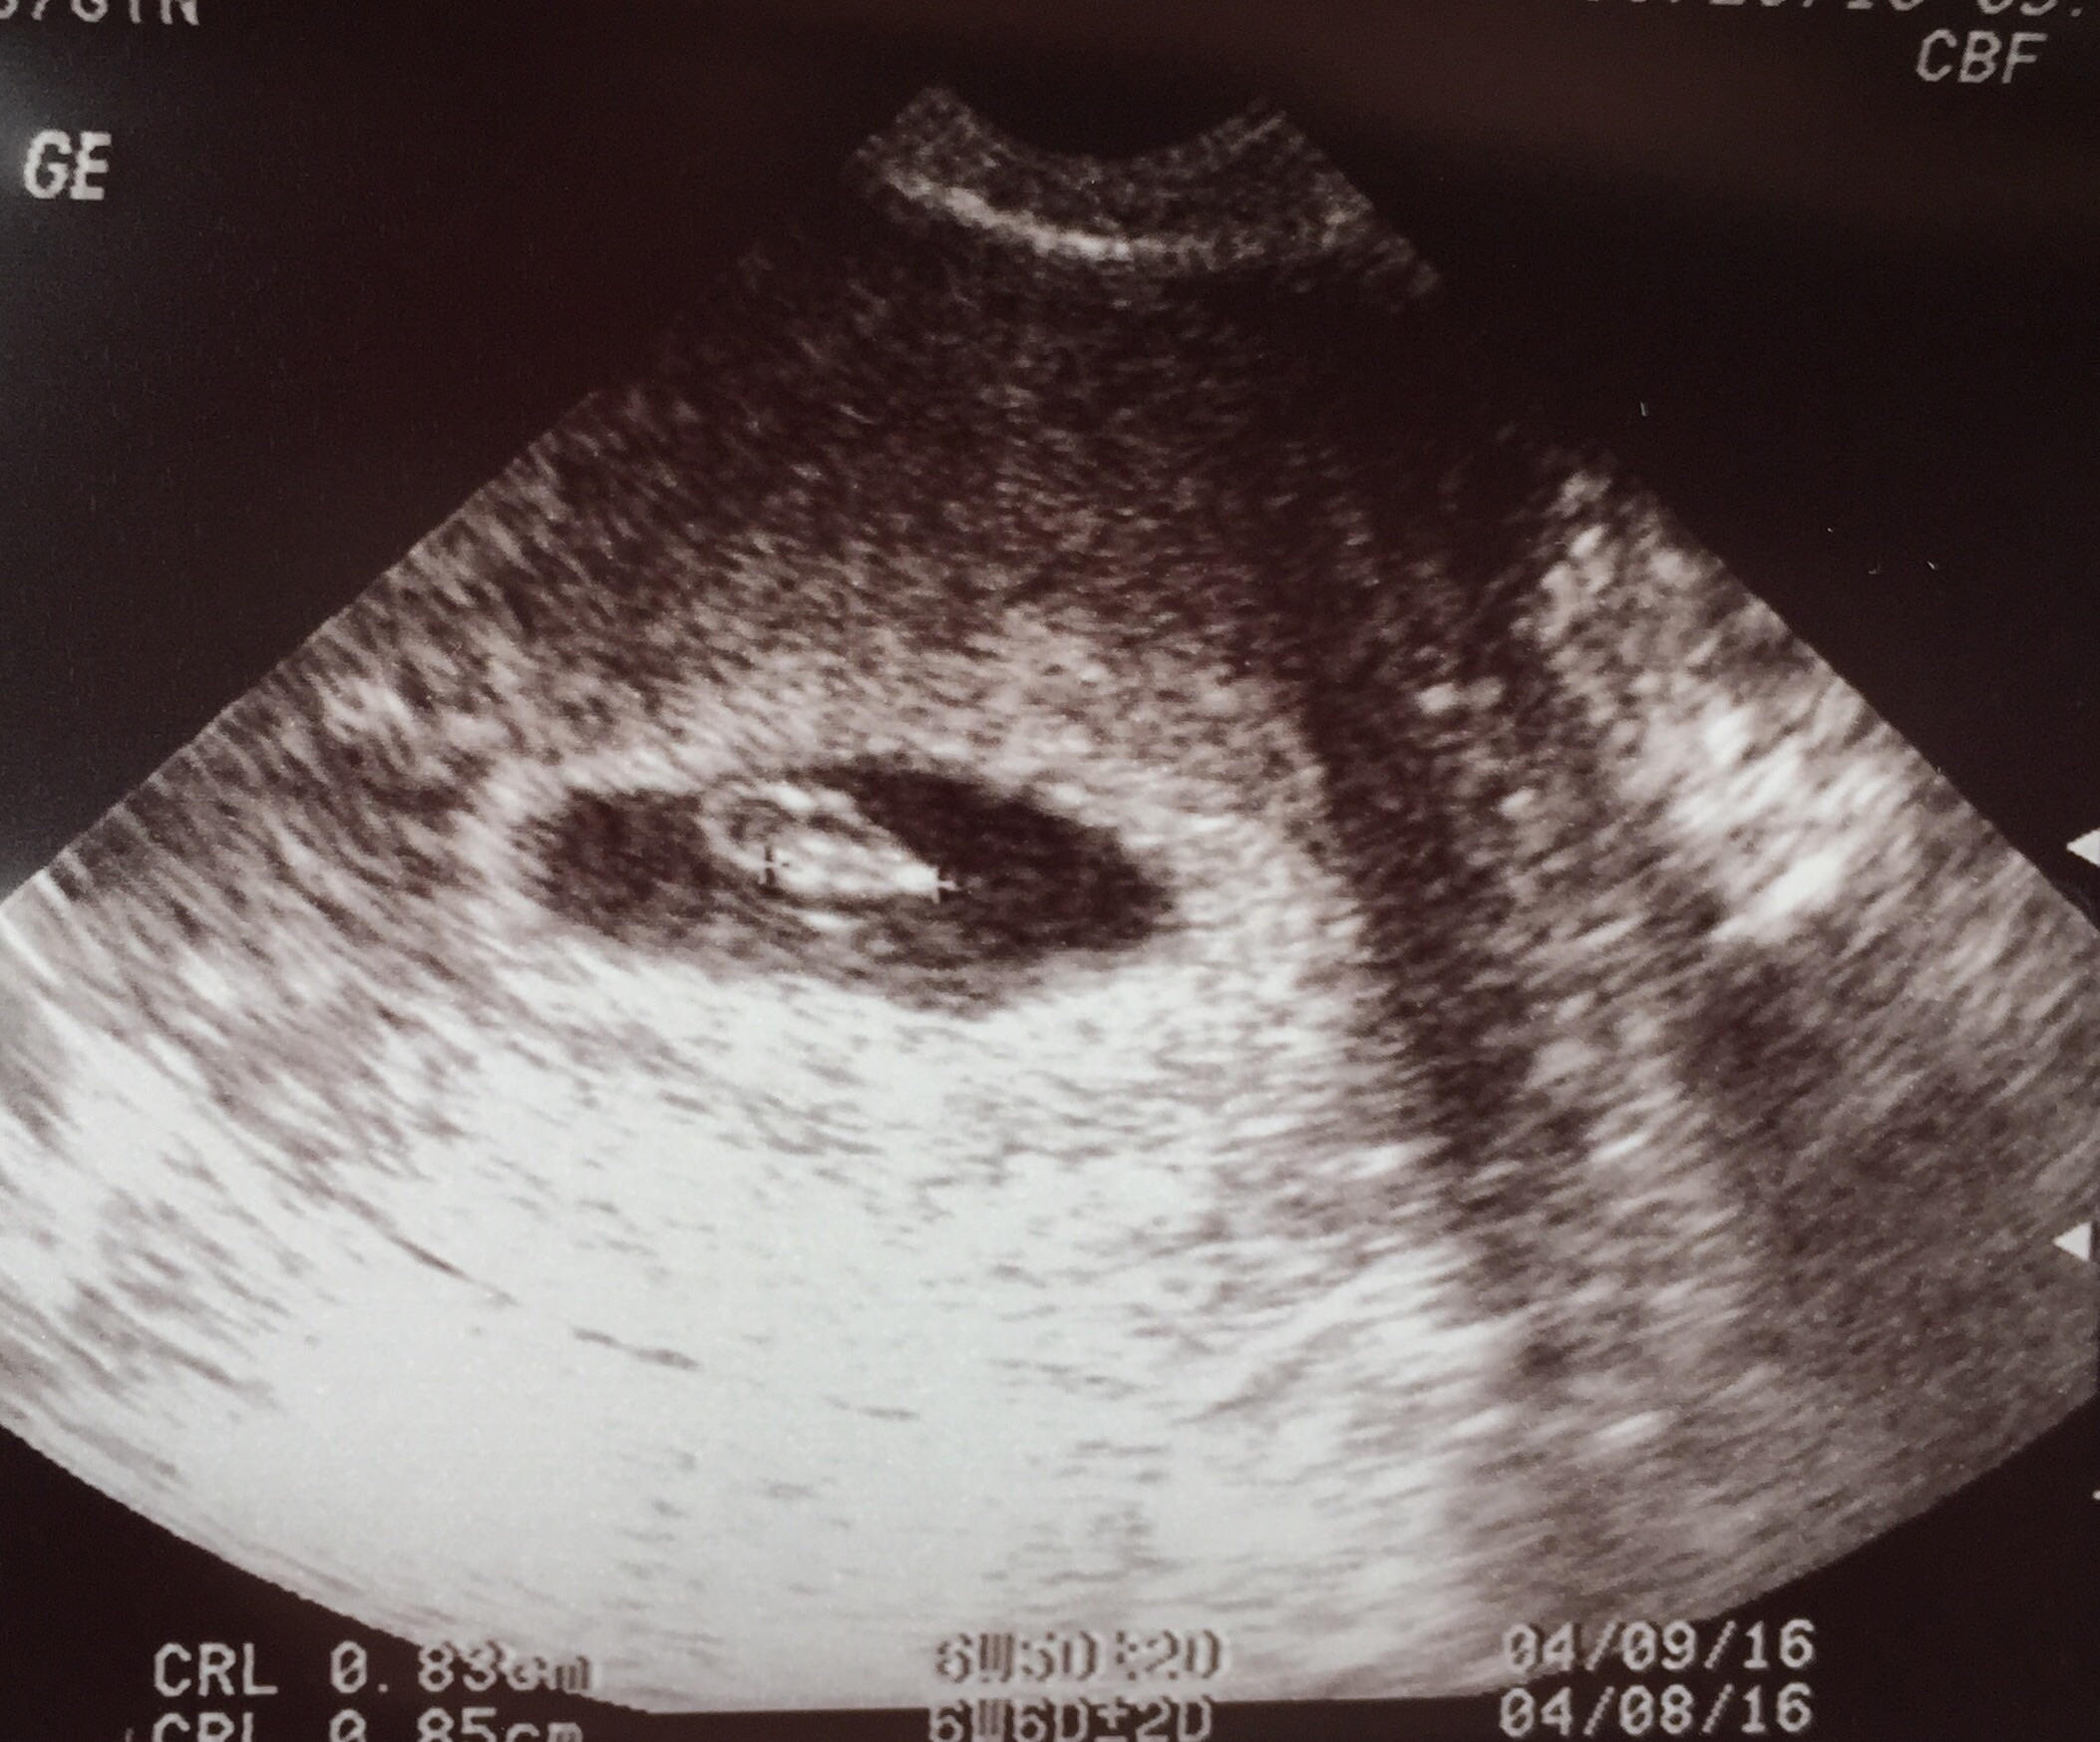

I had an early u/s at 5w3d and we just saw to empty sac and that was expected. Last Thursday we had another one and we are expecting our rainbow babies .

I had an early u/s at 5w3d and we just saw to empty sac and that was expected. Last Thursday we had another one and we are expecting our rainbow babies